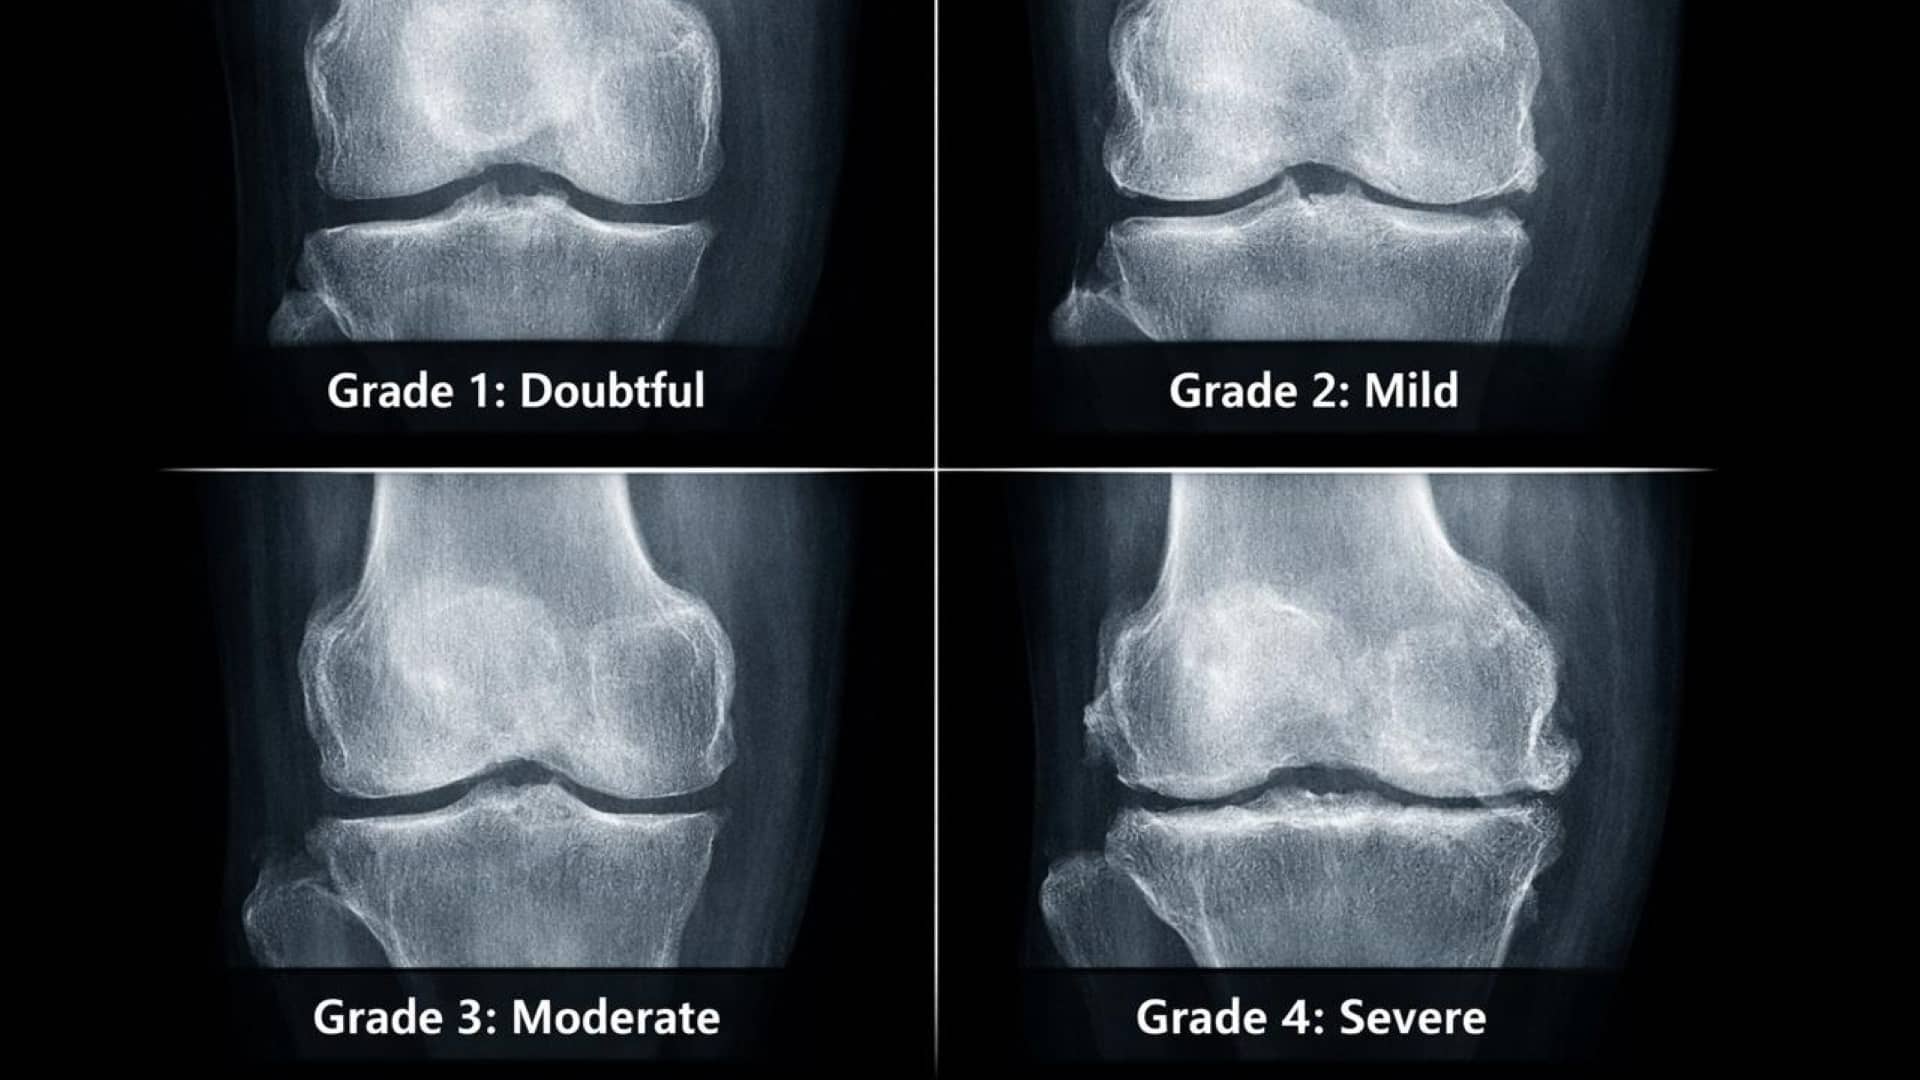

The Kellgren-Lawrence (K-L) Classification System

Orthopedic specialists use the K-L grading system to quantify this progression and determine the appropriate level of intervention:

- Grade 1 (Doubtful): Minimum bony lipping; the beginning of the process.

- Grade 2 (Mild): Definite bone spurs are present, but the “gap” between bones is still healthy.

- Grade 3 (Moderate): Moderate narrowing of the joint space. The bones are beginning to rub.

- Grade 4 (Severe): “Bone-on-bone” contact. Large spurs and significant hardening of the bone.